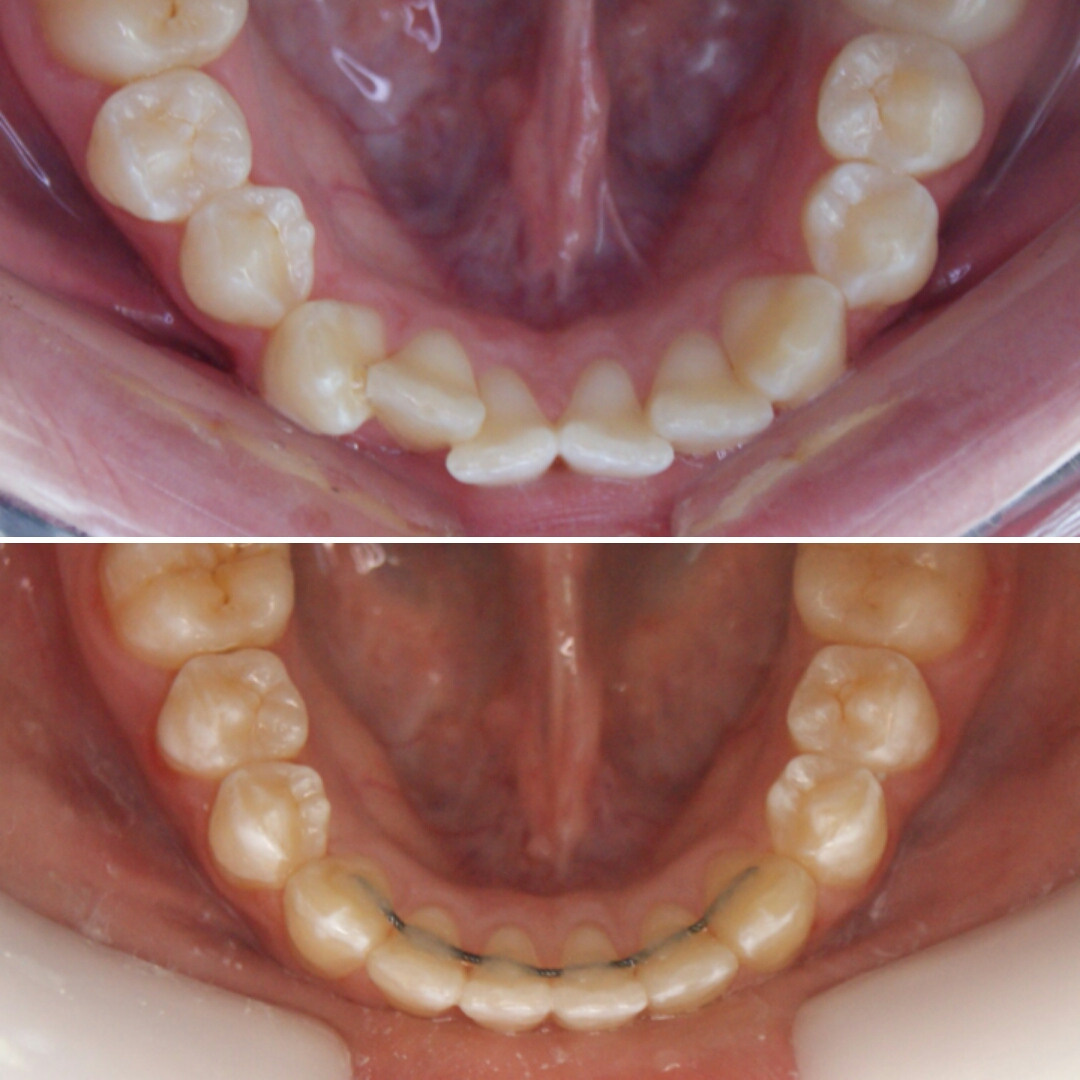

Эта фраза знакома многим ответственным родителям, которые привели на приём к ОРТОДОНТУ своего ребёнка в 5-10 лет, заподозрив проблему или понимая, что места постоянным зубам откровенно не хватает! Горькая правда в том, что брекеты - не волшебное средство от всех проблем, они "расставляют" зубы внутри сформированого объёма челюсти, но никак не влияют на её рост. Родители ждут, а тем временем драгоценное время, когда ребёнок растёт, уходит... Во взрослом возрасте приходится удалять здоровые зубы или прибегать к ортогнатической хирургической операции. 📸 На фото узкая нижняя челюсть, места постоянным зубам нет, боковые резцы прорезываются "вторым рядом".

✅ Помогаем с помощью расширяющей дуги, пружины и зацепных элементов, которые зафиксированы на МОЛОЧНЫЕ зубы